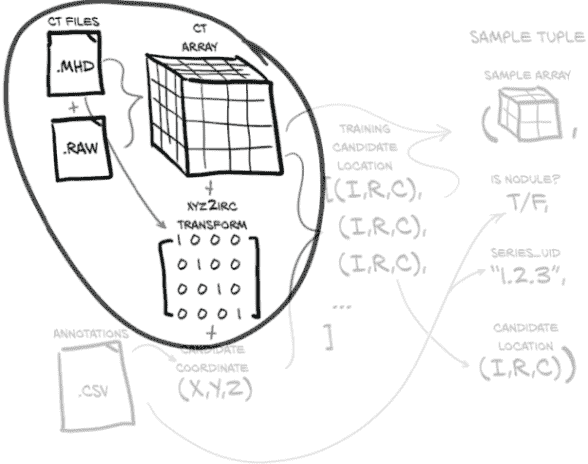

我们的目标是能够根据我们的原始 CT 扫描数据和这些 CT 的注释列表生成一个训练样本。这听起来可能很简单,但在我们加载、处理和提取我们感兴趣的数据之前,需要发生很多事情。图 10.2 展示了我们需要做的工作,将我们的原始数据转换为训练样本。幸运的是,在上一章中,我们已经对我们的数据有了一些理解,但在这方面我们还有更多工作要做。

图 10.2 制作样本元组所需的数据转换。这些样本元组将作为我们模型训练例程的输入。

我们的Ct类将消耗这两个文件并生成 3D 数组,以及转换矩阵,将患者坐标系(我们将在第 10.6 节中更详细地讨论)转换为数组所需的索引、行、列坐标(这些坐标在图中显示为(I,R,C),在代码中用_irc变量后缀表示)。现在不要为所有这些细节担心;只需记住,在我们应用这些坐标到我们的 CT 数据之前,我们需要进行一些坐标系转换。我们将根据需要探讨细节。

我们还将加载 LUNA 提供的注释数据,这将为我们提供一个结节坐标列表,每个坐标都有一个恶性标志,以及相关 CT 扫描的系列 UID。通过将结节坐标与坐标系转换信息结合起来,我们得到了我们结节中心的体素的索引、行和列。

使用(I,R,C)坐标,我们可以裁剪我们的 CT 数据的一个小的 3D 切片作为我们模型的输入。除了这个 3D 样本数组,我们必须构建我们的训练样本元组的其余部分,其中将包括样本数组、结节状态标志、系列 UID 以及该样本在结节候选 CT 列表中的索引。这个样本元组正是 PyTorch 从我们的Dataset子类中期望的,并代表了我们从原始原始数据到 PyTorch 张量的标准结构的桥梁的最后部分。